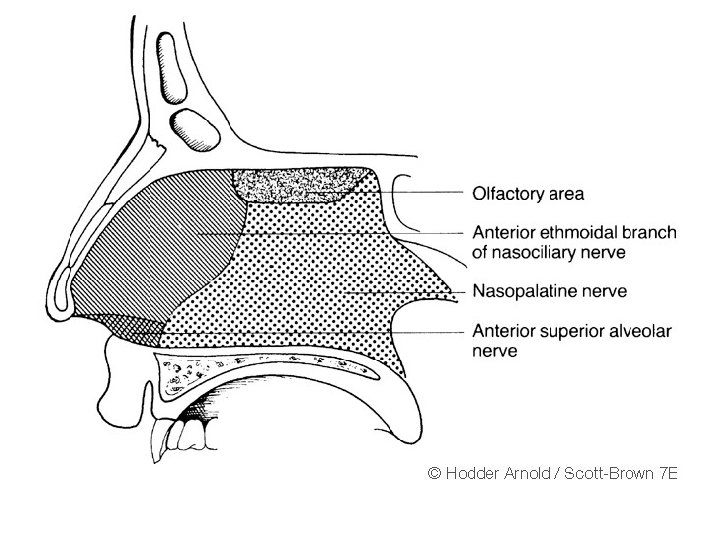

• Trigeminal nerve carries the common sensation via ophthalmic and maxillary divisions. • Special sensory (smell) carried via olfactory nerves.